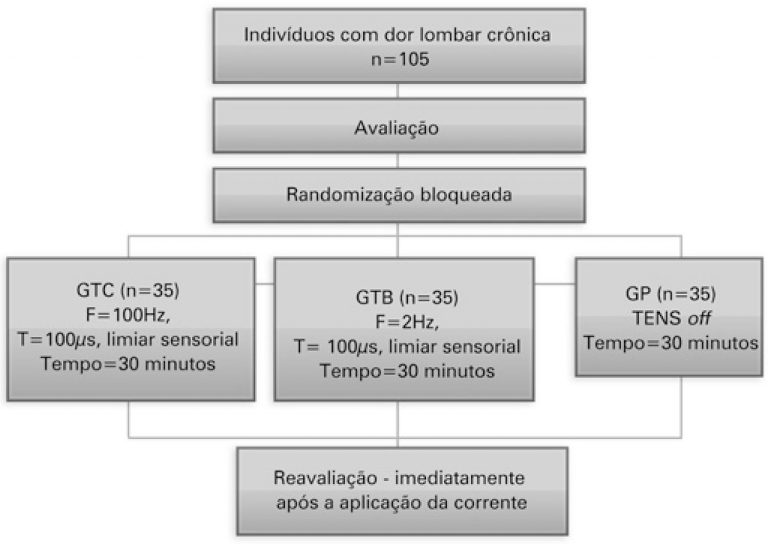

Efeito analgésico imediato de dois modos da estimulação elétrica transcutânea em indivíduos com dor lombar crônica: ensaio clínico controlado e randomizado

einstein (São Paulo). 03/dez/2021;19:eAO6027.

Efeito analgésico imediato de dois modos da estimulação elétrica transcutânea em indivíduos com dor lombar crônica: ensaio clínico controlado e randomizado

DOI: 10.31744/einstein_journal/2021AO6027

RESUMO Objetivo Comparar e avaliar o efeito analgésico da estimulação elétrica nervosa transcutânea convencional e do burst em pacientes com dor lombar crônica. Métodos Ensaio clínico controlado, randomizado, três braços e cego. Um total de 105 pacientes com dor lombar crônica não específica, com idade entre 18 a 85 anos foram distribuídos randomicamente nos seguintes grupos: Grupo Placebo (estimulação elétrica simulada), estimulação elétrica nervosa transcutânea convencional (estimulação contínua de 100Hz, 100µs, intensidade sensorial) e estimulação elétrica nervosa transcutânea burst (estimulação […]

Palavras-chave: Dor crônica; Dor lombar; Estimulação elétrica nervosa transcutânea; Medição da dor; Modalidades de fisioterapia